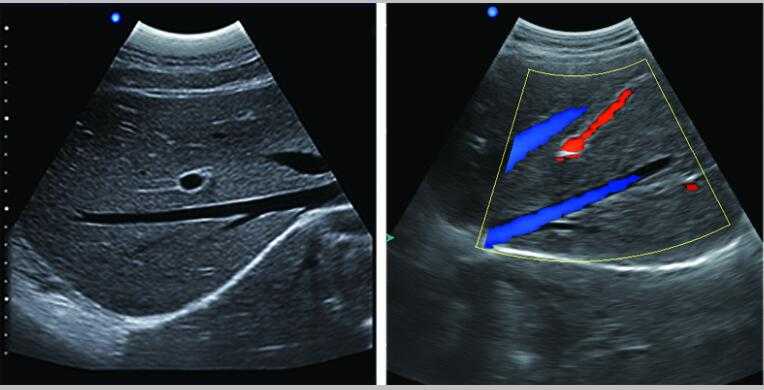

L3-VET筆記本式獸用B超機

牛羊馬豬犬貓及多種家禽、實驗動物、野生動物、及部分水生動物

L3-VET便攜筆記本式獸用B超機適用探頭